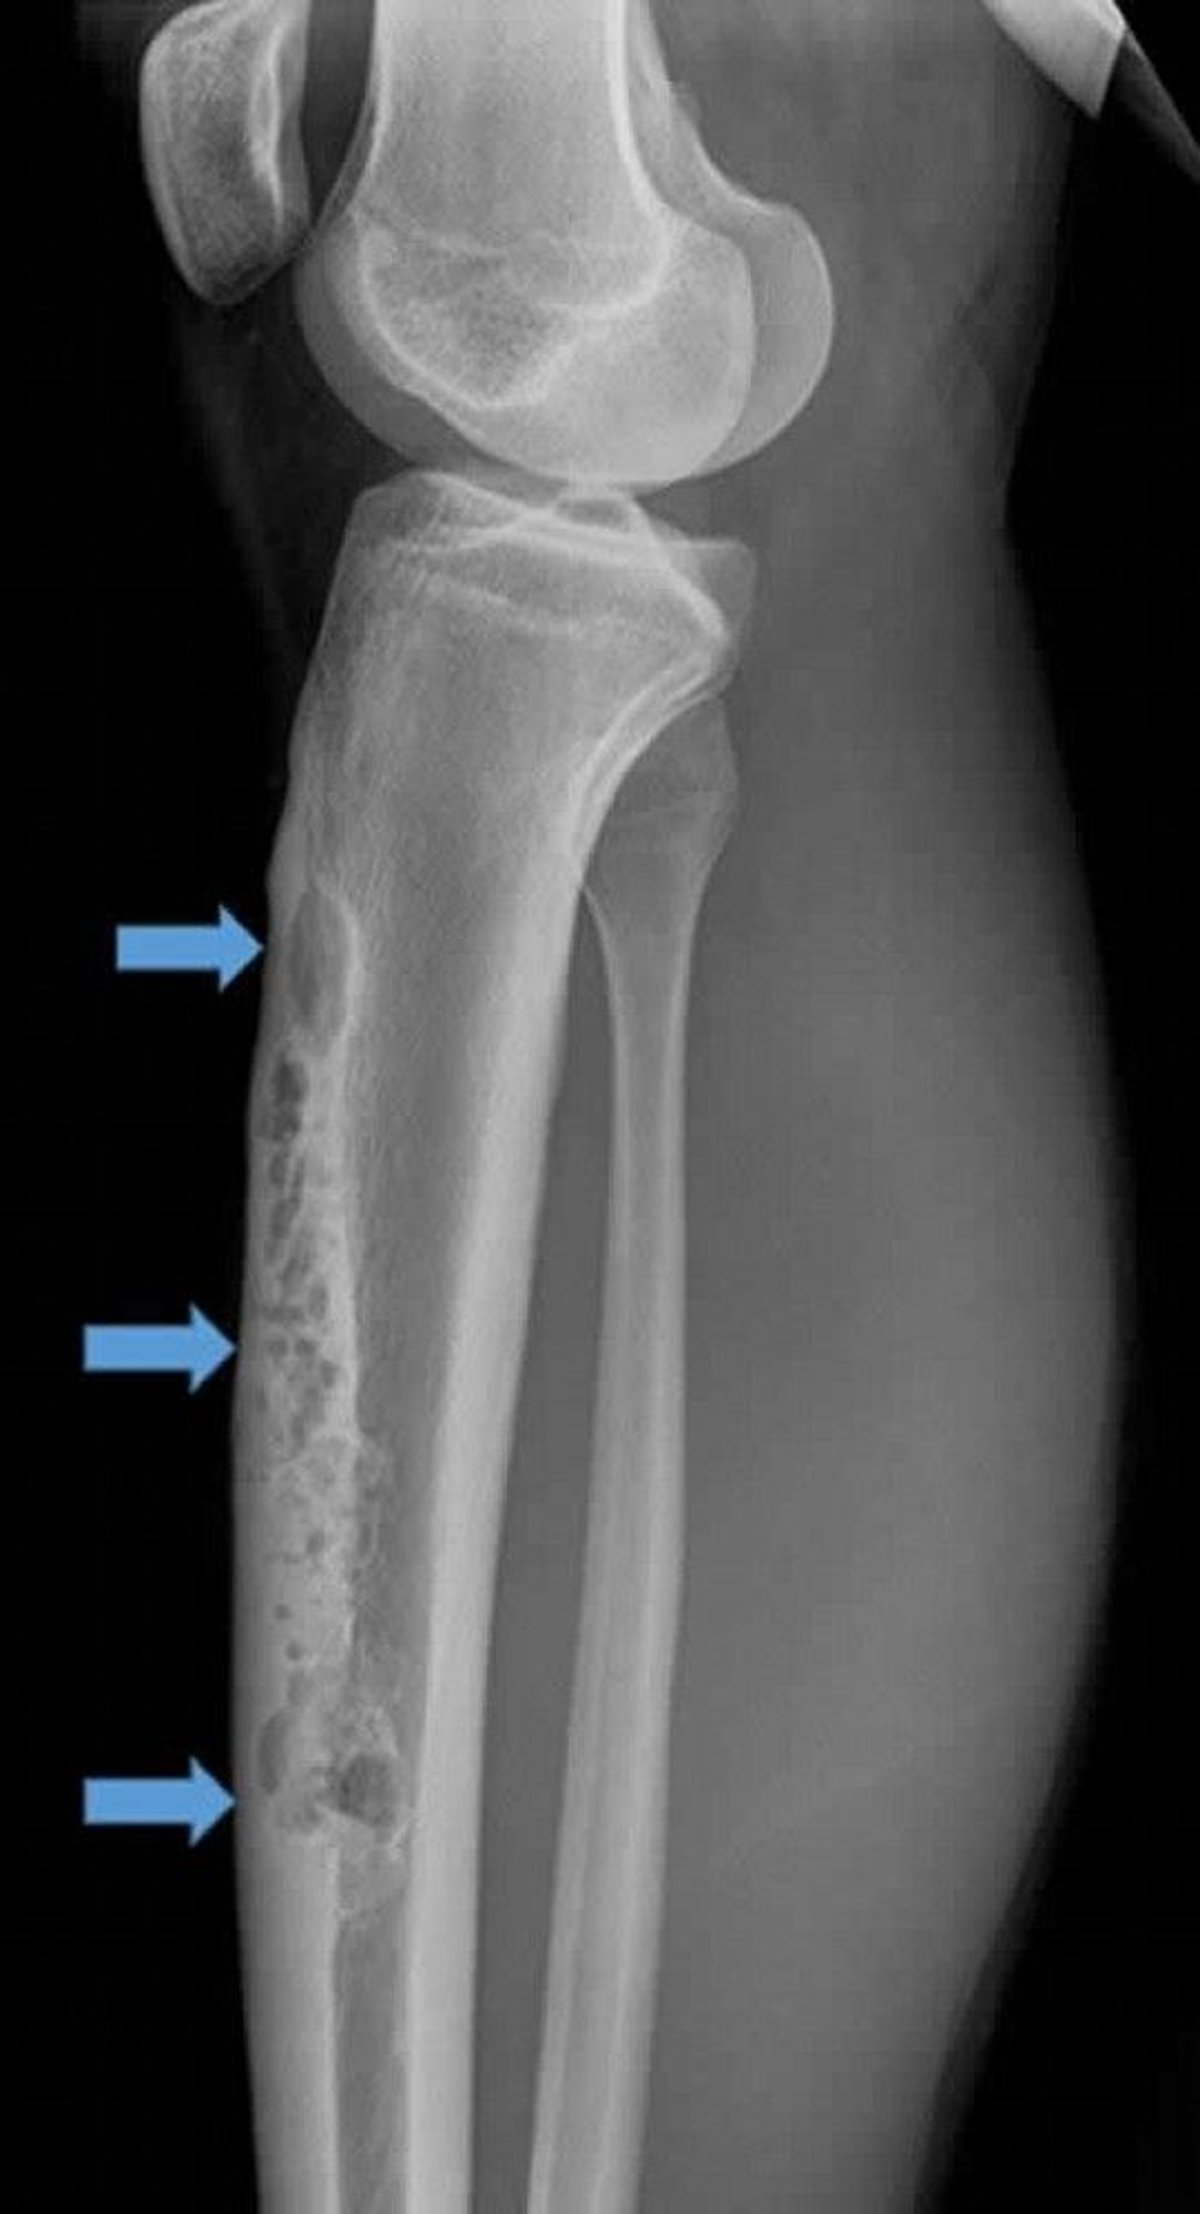

This lateral radiograph of right tibia shows a large anterior intracortical adamantinoma (arrows). Note the permeative, osteolytic "soap bubble" appearance.

Image courtesy of Michael J. Joyce, MD, and Hakan Ilaslan, MD.